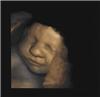

Las madres pueden proteger a sus hijos de los efectos de la pobreza 29/09/2011Los adultos que han vivido una infancia de pobreza a menudo presentan más problemas de salud que otras personas, como frecuentes resfriados o enfermedades cardiacas. Sin embargo, un estudio reciente señala que existe un factor que puede evitarles este destino: una buena madre. Esto es lo que ha revelado una investigación llevada a cabo por especialistas de la University of British Columbia, en Canadá. En el estudio se analizaron datos de un total de 1.215 adultos de una edad media de 46 años. Los cuidados de los que estos adultos habían disfrutado durante su infancia fueron evaluados mediante cuestionarios, en los que los participantes puntuaron el nivel de atención que les habían proporcionado de pequeños sus padres. Los resultados obtenidos demostraron que el riesgo de padecer enfermedades en la edad adulta, como consecuencia de haber crecido en la pobreza, quedaba compensado por los cuidados de la madre durante la infancia, en concreto, por su atención, por su interés en el bienestar emocional de los niños, por su tiempo de dedicación y por su amor y cariño. La capacidad de protección materna, y su efecto en la salud a largo plazo, estaría relacionada con la reducción y la gestión del estrés de los niños durante su infancia, señalan los investigadores. Según ellos, los adultos pueden enseñar a los niños a afrontar las tensiones con mayor efectividad, pueden ayudarlos a desarrollar respuestas emocionales más apropiadas o proporcionarles el sentimiento de que el mundo es, generalmente, un lugar seguro. “Podemos hacer mucho por ayudar a los niños a pasar los malos momentos. Y esta ayuda permanecerá, en su cuerpo y en su alma, durante toda la vida”, añaden los autores de la investigación. Más información Los Manuscritos del Mar Muerto ya pueden verse en Internet 29/09/2011Con la ayuda de Google, se han hecho públicas en la web imágenes de alta resolución de los Manuscritos del Mar Muerto, albergados en el Museo de Israel, en Jerusalén. Gracias a esta iniciativa, profesionales y estudiantes podrán a partir de ahora acceder a imágenes de 1.200 megapíxeles, de un total de cinco pergaminos. Los pergaminos publicados son el Pergamino Templo (con planos de la construcción y funcionamiento del Templo, originariamente escrito en fino cuero); el Pergamino Guerra (sobre la lucha de los “Hijos de la luz” contra los “Hijos de las tinieblas”); el Pergamino de Reglas de la Comunidad (un manual de disciplina); el Pergamino Gran Isaías (versión hebrea del libro de Isaías); y el Pergamino de Comentarios de Habakuk (con comentarios sobre el libro de Habakuk). Los Manuscritos del Mar Muerto fueron descubiertos entre 1947 y 1956 en el interior de 11 cuevas situadas a lo largo de las orillas del Mar Muerto, al este de Jerusalén. Estos pergaminos contienen las copias más antiguas de muchos textos bíblicos, y también muchos textos seculares relativos a la vida entre los siglos I y II de la era cristiana. Más información Científicos demuestran que las cremas antienvejecimiento no funcionan 28/09/2011Científicos de Francia, Alemania, Hungría, Reino Unido y Estados Unidos han reunidos pruebas de que ciertas proteínas que se creía que alargaban considerablemente la vida de numerosos organismos, en realidad no repercuten en la longevidad de los animales. Las cremas antienvejecimiento, que actúan sobre los genes que producen dichas proteínas (conocidas como sirtuínas), por tanto, no funcionarían como prometen los anuncios. En la industria de la belleza, muchos creen que los genes que codifican las sirtuínas, descritos a menudo como los «genes de la longevidad», son activados por el resveratrol, un fármaco derivado de plantas que se encuentra en concentraciones marginales en el vino tinto. Sin embargo, esta nueva investigación ha demostrado que dicha creencia carece de fundamentos sólidos. Según los investigadores, las pruebas fueron obtenidas en evaluaciones de experimentos previos que habían relacionado las sirtuínas con la longevidad de animales. Aparentemente, ninguno de estos experimentos resiste un análisis a fondo. Más información Nace la Red Española Matemática-Industria 28/09/2011El próximo viernes, 30 de septiembre, se constituirá en Santiago de Compostela la Red Española Matemática-Industria (math-in.net), con participación de profesores de Matemáticas de la Facultad de Ciencia y Tecnología (UPV/EHU). Se trata de una estructura asociativa que estará formada por grupos de investigación de toda España vinculados a la transferencia de tecnología matemática a la industria. Su principal misión será aumentar la presencia de los métodos y técnicas matemáticas en el sector productivo, impulsando la participación de los grupos de investigación del ámbito de las Matemáticas en proyectos estratégicos colaborativos con la industria. Al acto de presentación de la Red asistirán los rectores de las Universidades de Santiago de Compostela y A Coruña, Juan Casares Long y José María Barja, respectivamente; así como el director general de I+D+i de la Xunta de Galicia, Ricardo Capilla Pueyo, y el subdirector general de Fomento de la Innovación Empresarial del Ministerio de Ciencia e Innovación, Luis Cueto Álvarez de Sotomayor. En él intervendrán además la presidenta de la Red, la catedrática de Matemática Aplicada de la Universidade de Santiago de Compostela Peregrina Quintela, quien explicará en que consiste la Red y cuales son sus principales objetivos y resultados esperados y el consejero delegado de FerroSolar, Ramón Ordás, que se centrará en las ventajas para la industria de esa colaboración. Entre el público se contará con la asistencia de los presidentes de la Real Sociedad Matemática Española y de la Sociedad de Estadística e Investigación Operativa, representantes de la Sociedad Española de Matemática Aplicada, investigadores, representantes de las universidades integrantes de la Red, representantes de los gobiernos de las Comunidades Autónomas a las que pertenecen los grupos que forman parte de la Red, así como representantes de las empresas y centros tecnológicos colaboradores. Continuación del proyecto Consolider Ingenio Mathematica Esta Red nace como una evolución del proyecto Consolider Ingenio Mathemática (i-MATH), que está a punto de finalizar, y a través del que se ha desarrollado una ingente labor de difusión, información y establecimiento de relaciones entre la universidad y la empresa. A raíz de esta intensa actividad surgieron un número importante de colaboraciones y contratos entre los grupos de investigación y la industria, que se verá incrementado en los próximos años. Dado que el marco temporal del proyecto Consolider Ingenio Mathematica termina en abril de 2012, la creación de esta Red permitirá dar continuidad a esta actividad y aprovechar las oportunidades surgidas del proyecto. Investigación matemática orientada hacia la empresa En los últimos 14 años los grupos de investigación vinculados a transferencia de tecnología matemática firmaron un elevado número de contratos directos con empresas, más de 400, e impartieron cerca de 200 cursos de formación dirigidos a centros tecnológicos y a empresas. Estos contratos le permitieron a la universidad obtener una financiación privada de cerca de 10 millones de euros. Desarrollaron 111 paquetes de software propio, de los que el 40% fueron transferidos a la industria. Además, estos grupos tienen una amplia experiencia en transferencia a sectores como las Administraciones Públicas, Informática y Comunicaciones, Logística, Economía y Finanzas, Energía, Materiales y Medio Ambiente. Estos datos, extraídos de la Encuesta de Oferta Tecnológica por Grupos o Entidades de Investigación realizada en el marco del proyecto i-MATH, ponen de relieve que una parte importante de la actividad realizada por estos grupos de investigación está orientada a la industria. No obstante, es necesario continuar con esta labor con el objetivo de acercar la tecnología matemática a un mayor número de empresas y, sobre todo, sensibilizarlas sobre la necesidad de aplicación de estas técnicas. Más información Aumentan los casos de “sextorsión” en España e Iberoamérica 26/09/2011A mediados de 2010 los medios de comunicación estadounidenses comenzaban a hacerse eco de un aviso lanzado por fiscales, expertos en seguridad en Internet y diversas agencias policiales: se había detectado un auge importante en el número de casos de un nuevo delito online que denominaban “sextorsión”. Ante estos mensajes, la iniciativa PantallasAmigas activó una acción específica de prevención y detección. Un año después se ha constatado un aumento exponencial en las denuncias recibidas desde España y otros países iberoamericanos. La “sextorsión” es un acto de chantaje que se inicia cuando una persona posee o dice poseer imágenes íntimas de otra a la que amenaza con hacerlas públicas o con enviárselas a sus contactos si no accede a sus pretensiones. “Durante el pasado mes de agosto nos han llegado siete casos de este tipo», ha declarado Jorge Flores, director de PantallasAmigas. Fiscalías españolas han comenzado a lanzar también la voz de alarma: «No tenemos datos estadísticos todavía y no hay una denuncia en masa de casos de este tipo —entre otros motivos porque la víctima se siente avergonzada por lo sucedido— pero es un delito que relaciona menor y nuevas tecnologías que estamos empezando a registrar», afirmó a los medios el mayo pasado Gema García, fiscal delegada de Menores de Valencia. Según informó García, la edad a la que se empieza a ser vulnerable a este delito es la pubertad, cuando los menores se inician en las relaciones sexuales; la mayoría de las víctimas son chicas, añadió. Pese a no existir registros específicos sobre este tipo de delitos, entidades como PantallasAmigas realizan un seguimiento de estos nuevos riesgos tecnológicos desde su aparición en otros países para mejorar la prevención y la alerta temprana en nuestra sociedad. Según un estudio publicado por INTECO en 2010, el 8% de los menores españoles recibe de fotos o vídeos de chicos/as de su entorno en posturas provocativas o inapropiadas, niveles de sexting que coinciden con los detectados por otras fuentes. El objetivo del sextorsionador no es en todos los casos obtener más pornografía producida por la víctima: también es habitual que exijan un pago en dinero, o que pretendan forzar sexualmente a su víctima. Para Jorge Flores, los consejos fundamentales para no ser víctimas de una sextorsión son «no protagonizar imágenes comprometedoras y proteger nuestra privacidad e intimidad y las de nuestros contactos mediante medidas activas y pasivas de seguridad en nuestro ordenador y teléfono móvil». Se evitaría así, en su opinión, que se diese alguna de las dos condiciones necesarias: que la imagen sea tomada y que la imagen llegue a manos criminales. Más información La NASA advierte sobre nuevas explosiones solares 26/09/2011La NASA ha publicado que la región de manchas solares 1302 lanzó una nueva y potente llamarada solar de categoría X1.9 la mañana del pasado 24 de septiembre. El Observatorio Solar Dynamics (SDO) de la NASA registró el flash ultravioleta extremo en diversas longitudes de onda. Asimismo, un vídeo sobre el evento ha mostrado la onda expansiva surgida en el lugar de explosión, que es señal de que ésta produjo una eyección de masa coronal o CME. Una CME es una onda formada por radiación y viento solar que se desprende del Sol en los periodos de Actividad Máxima Solar, que ocurren cada 11 años. Esta onda es muy peligrosa ya que, si llega a la Tierra y su campo magnético está orientado al sur, puede dañar los circuitos eléctricos, los transformadores y los sistemas de comunicación, además de reducir el campo magnético de la Tierra por un período. Aunque la NASA advirtió ayer de que la CME del 24 de septiembre podría alcanzar el campo magnético de la Tierra hoy, día 26 de septiembre, también señala que hasta ahora las explosiones no han sido dirigidas hacia la Tierra. Esta situación, sin embargo, podría cambiar si las manchas solares giran hacia nuestro planeta en los próximos días. De hecho, las 1302 están creciendo y no muestran signos de que vayan a calmarse de manera inmediata. Más información Los neutrinos viajan a mayor velocidad que la luz, revela un experimento del CNRS 23/09/2011Mediciones realizadas por un equipo de investigadores del CNRS francés, en el marco del experimento internacional OPERA, parecen indicar que una partículas subatómicas denominadas neutrinos viajarían a mayor velocidad que la luz. En 1905, Einstein enunció su teoría de la relatividad y demostró que nada podía sobrepasar la velocidad de la luz en el vacío. A pesar de esto, un siglo después, y tras tres años de mediciones de alta precisión y de complejos análisis, el experimento OPERA ha alcanzado unos resultados completamente inesperados. Según los investigadores, los neutrinos tardaron una pequeña pero significativa cantidad de tiempo menos que la luz en recorrer la trayectoria entre el CERN de Ginebra y el Gran Sasso, en Italia, a través de un laboratorio subterráneo de más de 730 kilómetros. Concretamente, la luz recorre esa distancia en 2,4 milisegundos, y los neutrinos en 60 nanosegundos menos. En metros, al final del recorrido los neutrinos habían sacado a la luz una ventaja de 20 metros. Los científicos señalan que estos resultados son fiables por la enorme exactitud de las mediciones, y también porque las observaciones se hicieron sobre más de 15.000 neutrinos, pero no entienden cómo estas partículas han superado un límite de velocidad que hasta ahora se pensaba infranqueable. Más información Las industrias culturales son las locomotoras de la economía 23/09/2011